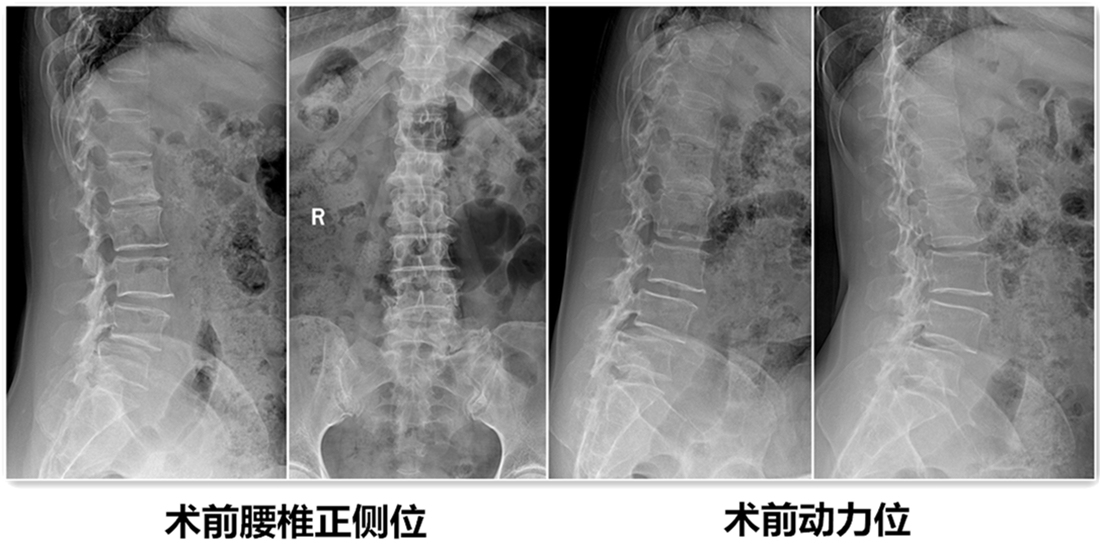

经检查该患者L4椎体退变性滑脱诊断较为明确,且伴有严重的椎管狭窄症状。由腰椎X线动力位片示腰椎不稳,腰椎融合术为最佳治疗方案。结合病人病情、年龄及身体条件,经腰椎间盘治疗中心团队反复论证,认为采取微创镜下融合术为最佳方案。刘维克主任介绍原本需要开放才能完成的手术现在微创下完成,需要攻克2个难点:一是需要在脊柱内镜下给予充分的减压,二是在微创通道下处理椎间盘和终板,并安全的植入融合器。

患者术后第3天带支具下床活动,症状基本消失,并行X线检查。见滑脱复位,且椎间隙高度恢复。